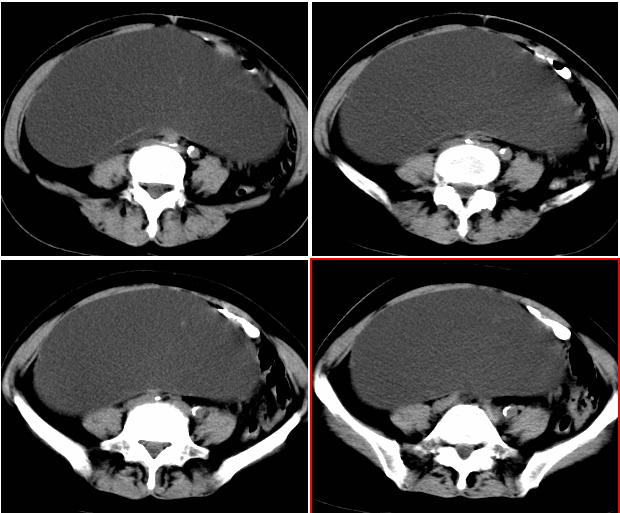

右侧后腹膜巨大囊性肿块影阴,边缘清晰,内见膜状分隔,均匀水样密度,右肾影阴消失,囊块所到区域脏器受挤移位,右侧输尿管扩张,应该考虑:右肾重读积水,巨大肾囊肿不除外。引发肾性高血压。

右侧重度肾积水,右侧输尿管扩张.原因待查.

从囊性低密度区的形态,及分布看我支持1楼战友的分析及诊断意见。{右恻输尿管全程扩张,阻塞位置应该在输尿管与膀胱的交界区,建议行膀胱镜检,楼主还是应该给患者作强化扫描!!!!!}

腹部巨大囊性占位,膨胀性生长,边界光整,囊内容物为水样密度,其内可见多发分隔,右恻输尿管全程扩张,纵观所有层面,正常右肾未见,考虑为来源于右肾的巨大多房性肾囊肿可能性大。

右侧巨大囊状无功能肾,输尿管积水(输尿管梗阻所致)。

右肾明显扩大,皮质菲薄,间隔细,右输尿管全程扩张,右肾重度积水,原因应重点查输尿管膀胱接合处。

右侧巨大囊状无功能肾,输尿管积水.右侧积水肾旁囊性病灶应该是左侧卵巢浆液性囊腺瘤.